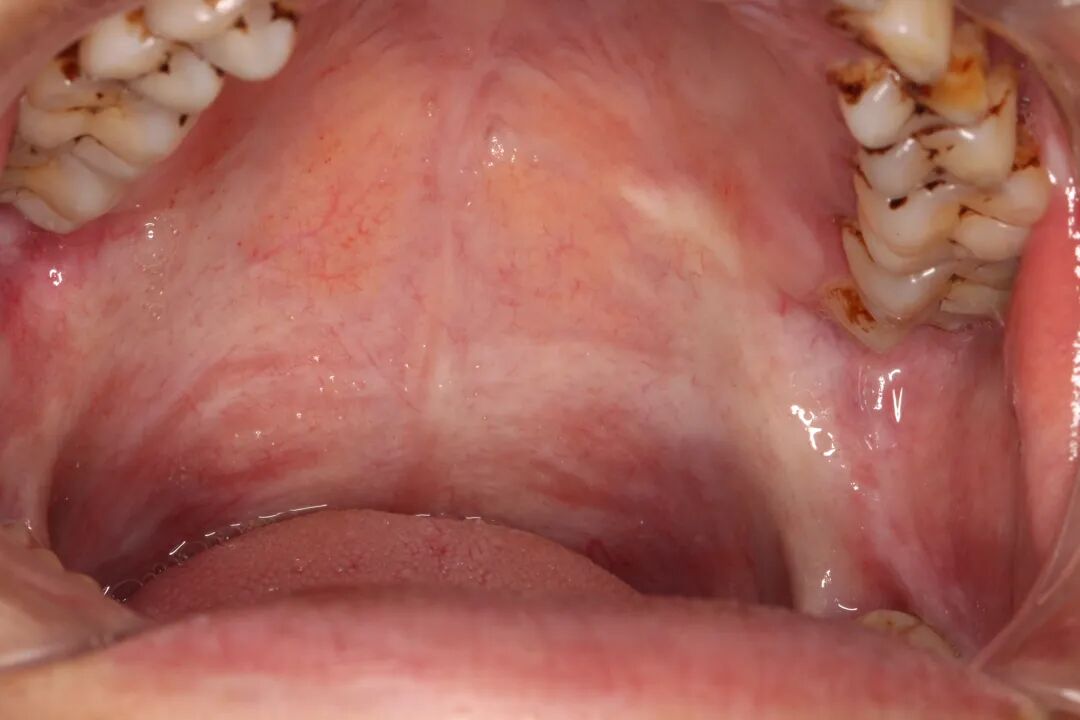

口腔黏膜下纤维性变(OSF)

“口腔黏膜下纤维性变是口腔癌的一种癌前状态。一旦口腔黏膜发生纤维化,治疗难度很大,目前临床上几乎没有办法逆转,无法恢复正常黏膜,仅可通过对症治疗改善症状。即使进行手术,也难取得很好的效果。

医生介绍,口腔黏膜下纤维性变具有较大的癌变风险,可以累及口腔内的任何地方,表现为口腔黏膜颜色苍白,严重时呈板状硬化,口腔疼痛、烧灼感,口腔溃烂,运动受限,功能异常等不同症状。

医生提醒,并不是所有OSF患者都有张口受限的症状。当症状不是特别明显时,也要警惕癌变的可能性。